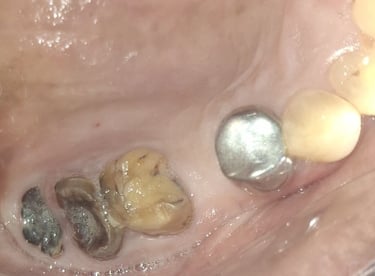

All images shown here represent real clinical cases of teeth extractions done at our dental clinic with patient consent.

Illustrative images and similar real clinical cases requiring tooth extraction